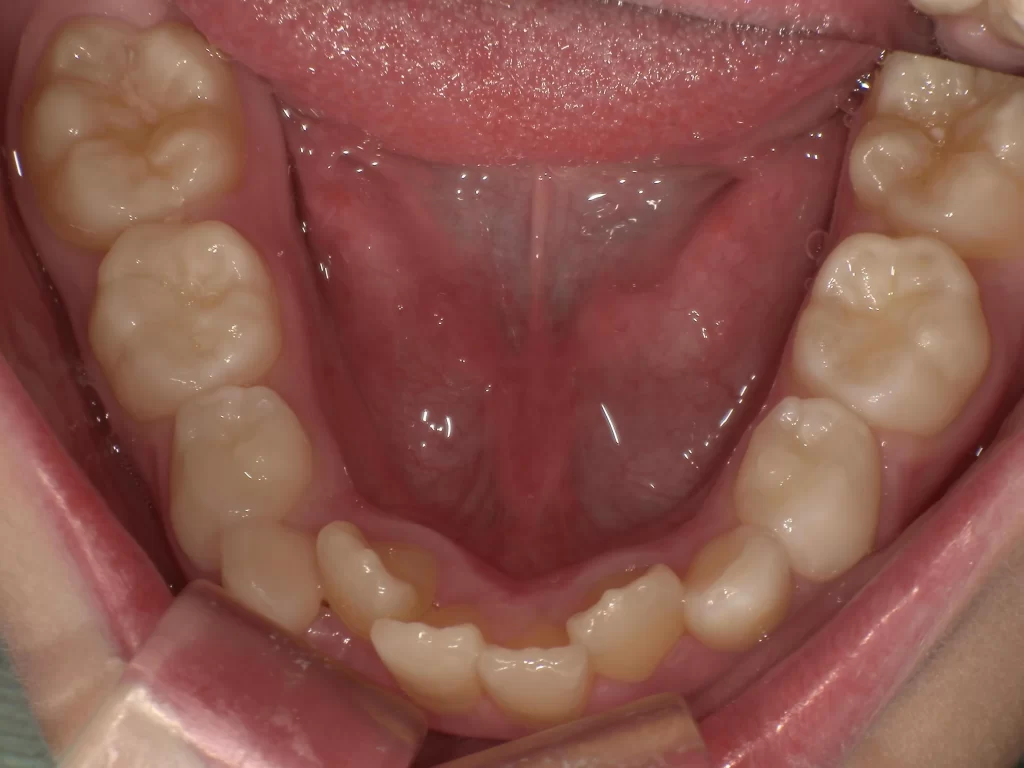

症例⑤:10歳・ガタガタ・出っ歯・深い噛み合わせ

【使用期間:3ヶ月】

歯が生えるスペースが足りずガタガタしており、噛み合わせも深い状態でした。

▼ 治療前(Before)

▼ 使用3ヶ月後(After)

- 年齢・症状: 10歳、叢生(ガタガタ)、過蓋咬合

- 治療法: プレオルソ

- 期間: 3ヶ月

- 結果: 装置を使うことで歯列の横幅が拡大し、ガタつきが自然に改善されました。深い噛み合わせも良くなっています。